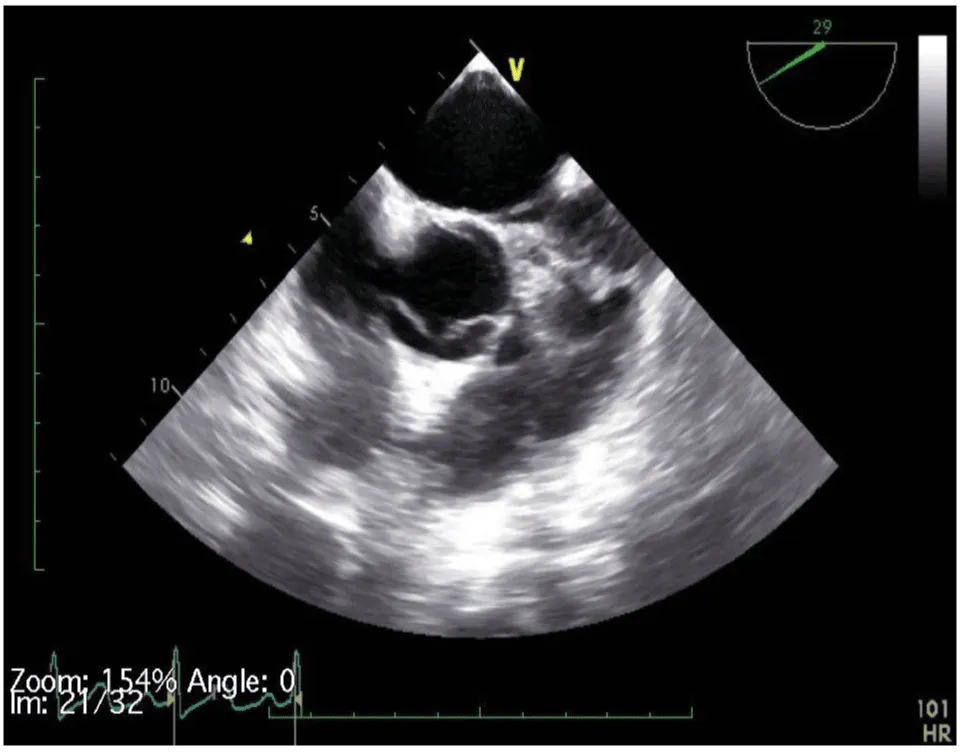

Her initial vital signs upon presentation to the hospital were; blood pressure: 161/76 mm Hg, heart rate: 96 beats per minute, respiratory rate: 27 breaths per minute. Physical exam revealed a cardiac auscultation findings of a grade 2 diastolic murmur which was loudest at the 2nd right intercostal space as well as a grade 2 systolic flow murmur. Cardiac biomarkers were elevated with initial troponin-I of 0.33 ng/mL, peak of 2.28 ng/mL and subsequent down trend. Electrocardiography (Figure 1) showed sinus rhythm with anterior and inferolateral T wave inversion and chest radiograph (Figure 2) was unremarkable. She underwent coronary angiography which revealed normal coronary arteries. The takeoff of the right coronary artery (RCA) was noted to be superior and anterior to its normal position (Figures 3A and 3B). Transthoracic and transesophageal echocardiography (TEE) revealed normal left ventricular systolic function and severe insufficiency of the aortic valve with Quadricuspid morphology (Figure 4A in Diastole, Figure 4B in Systole, Figure 4C Long Axis of the aortic valve). She underwent aortic valve replacement with a # 19mm ON-X mechanical valve. Intraoperatively it was noted that the ostium of the right coronary artery was over the aberrant leaflet. Her postoperative course was complicated by the development of supraventricular tachycardia, posteriorly localized pericardial effusion, severe hemolytic anemia, renal failure and pancreatitis leading to her death eleven days after the surgery.

Figure 4a: QAV in diastole (arrows pointing to 4 cusps).

The diagnosis of QAV was facilitated by TEE, which revealed the characteristic findings. The short axis views of the aortic valve are optimal for making the diagnosis of QAV. The classic X shaped commissural aortic valve pattern in diastole (Figure 4B) compared to the Y shape of a trileaflet valve is diagnostic (Figure 4D) [3].